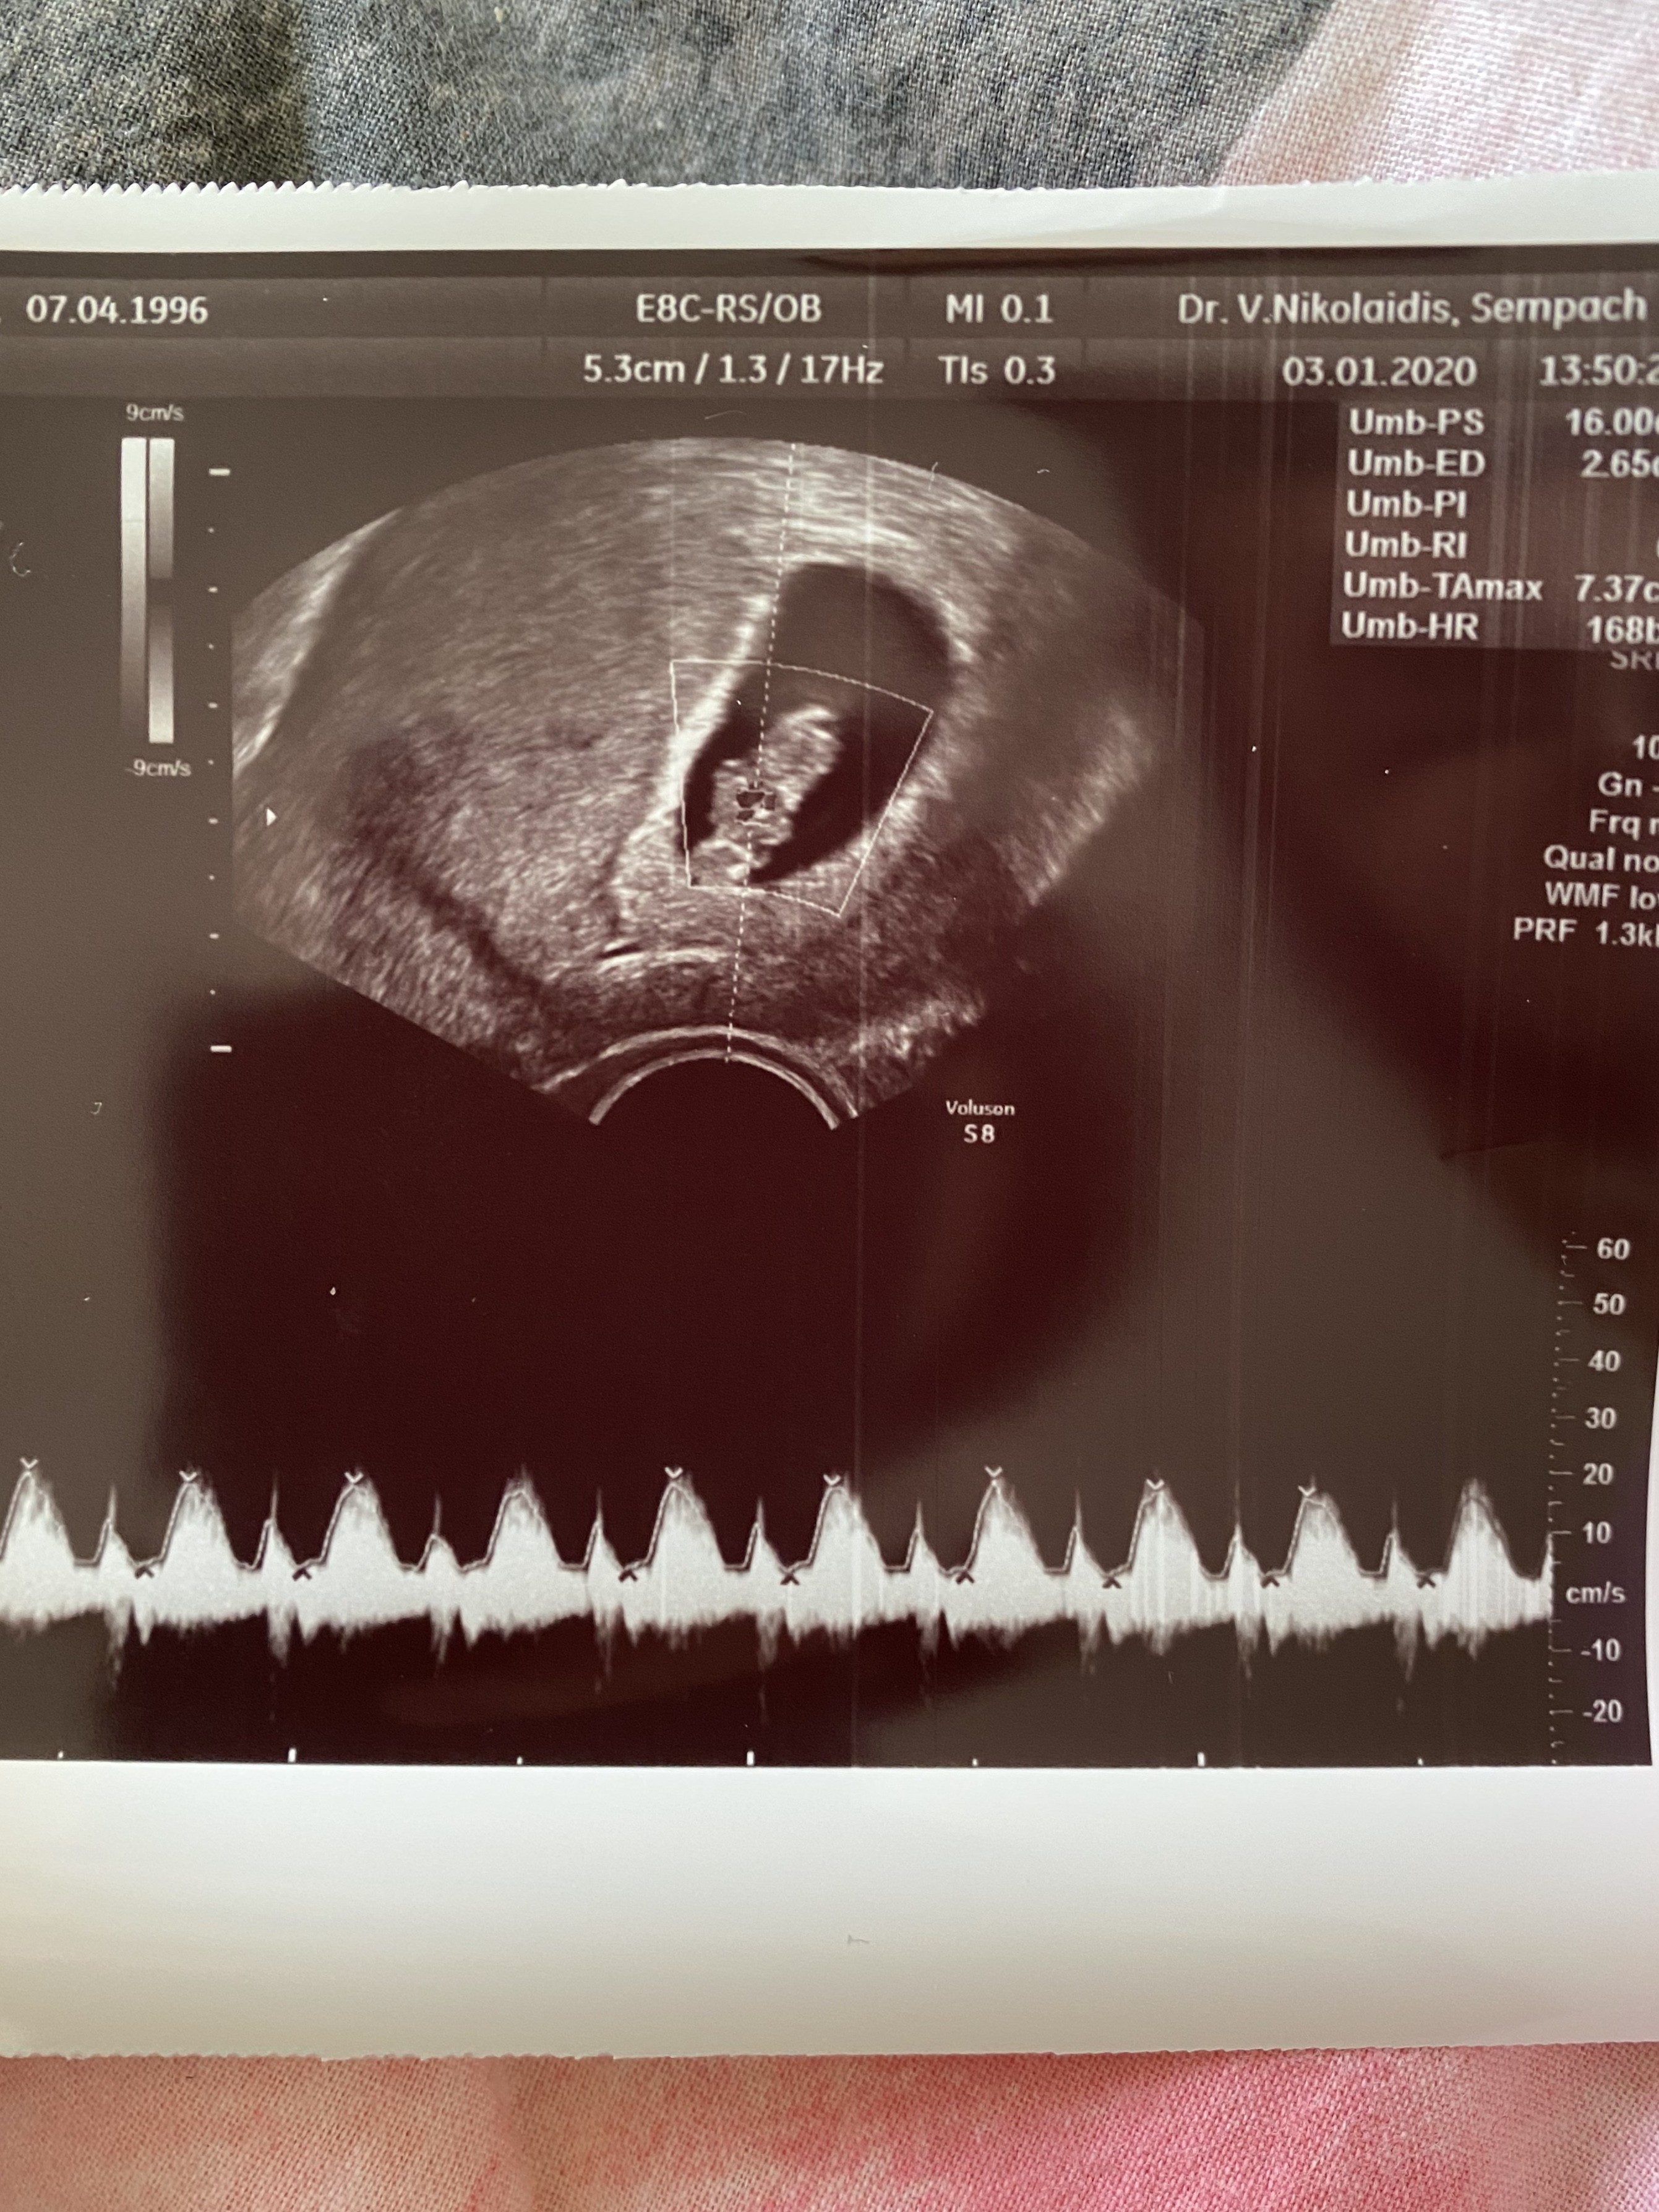

Hej dziewczyny! Nie zebym wierzyła w takie rzeczy, ale wczoraj na pierwszym usg w 8 tygodniu równo ginekolog powiedziala mi, ze bedzie chłopiec bo słyszy po biciu serca 😳 Teraz nie daje mi to spokoju. Wolałabym nie słyszeć tego aby sie nie nastawiać. Dodam ze mieszkam w Szwajcarii, a ona jest najlepsza w okolicy, ma swoja klinikę, robi prenatalne, odbiera porody i jak twierdzi - nigdy sie nie myli gdy juz widzi lub słyszy. Czy możecie wyslac mi zdjecia usg synków z 8 tygodnia ciazy z tętnem tak jak pokaże to na załączniku?

Nie wiem czy tak jest 🤷‍♀️ ale mój maluszek w 9 tygodniu miał tętno 170. W 12 tc okazało się, że będzie chlopczyk, ale na podstawie badania genetycznego. Teraz w 17 tc ma tętno 156 💓

mój maluch ma 168 w 9 tygodniu wlasnie, corka miala w tym tygodniu 190... Hmm oby sie potwierdziło za miesiac bo nie lubie sie nastawiać na jedno, a pozniej wyjdzie drugie. Oby zdrowe, ale ciagle mnie to trapi 😂